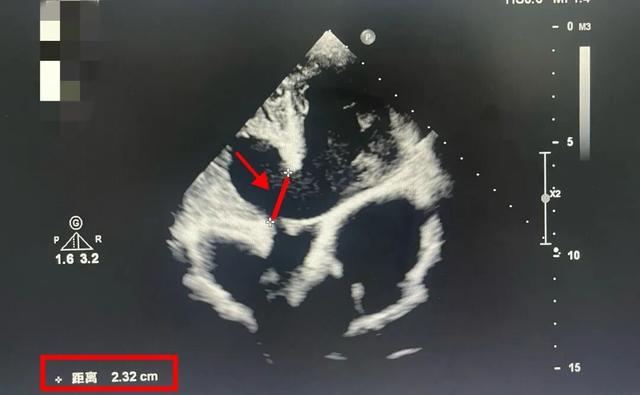

彼时,14岁的李小并不知道,他的心脏缺口已经“裂”开长达22毫米。

什么概念?室间隔缺口>5毫米,就一定要动手术“维修”了。

而李小心脏的这个裂口,已经超过正常手术指征的4倍。他的心脏射血分数已经低于50%(正常是50%-70%)。

红色线段标注出来的那一小截,就是李小的室间隔缺损缺口